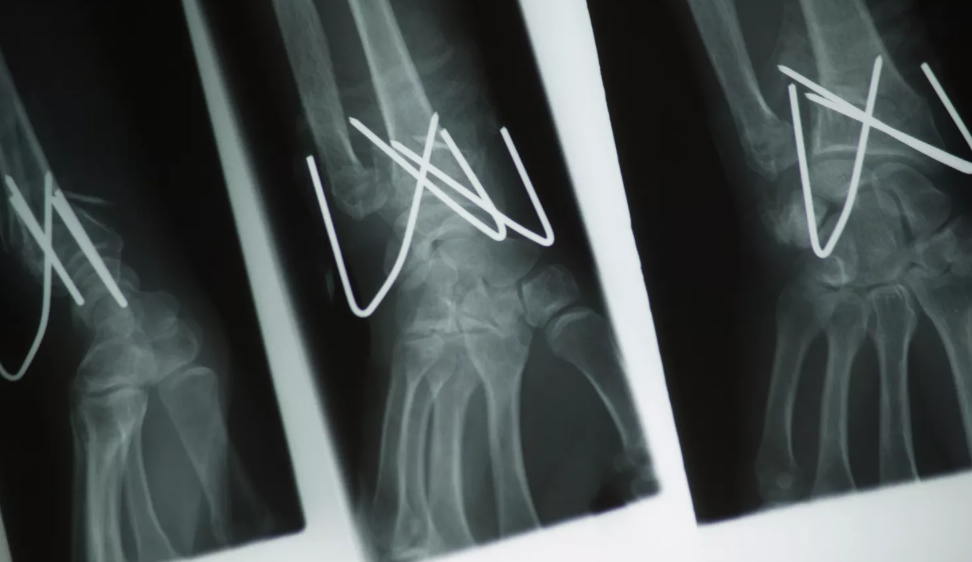

Os fios de Kirschner ou fios K são fios metálicos (aço inoxidável) afiados em uma ou ambas as extremidades, utilizados para manter fragmentos ósseos unidos (fixação por pino) ou para fornecer um ponto de ancoragem para tração esquelética.

O fio K (fio de Kirschner) é agora amplamente utilizado na ortopedia e em outros tipos de cirurgia. Esses fios podem ser inseridos através do osso para manter os fragmentos no lugar. Podem ser colocados percutaneamente (através da pele) ou enterrados sob a pele.

Os fios K são frequentemente usados para estabilizar um osso fraturado e podem ser removidos no consultório assim que a fratura cicatrizar. Alguns fios K são roscados, o que ajuda a evitar o movimento ou deslocamento do fio, embora isso também possa tornar sua remoção mais difícil.

O Fio K (Fio de Kirschner) é indicado para fixação de fraturas ósseas, reconstrução óssea e como pinos guia para inserção de outros implantes. O tamanho do pino escolhido deve ser adaptado à indicação específica. É necessária a avaliação do cirurgião para garantir que o Fio K (Fio de Kirschner) seja apropriado para a indicação.

A fiação em banda de tensão é uma técnica na qual os fragmentos ósseos são atravessados por fios K que, posteriormente, também servem como ancoragem para uma alça de fio flexível. Ao apertar a alça, os fragmentos ósseos são comprimidos uns contra os outros. Fraturas da rótula e do processo olecraniano do cotovelo são comumente tratadas por este método.